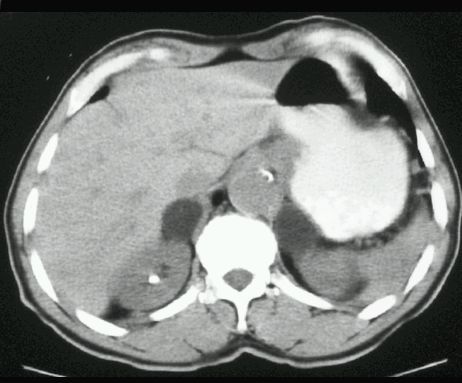

TK

GRUCZOLAK NADNERCZA